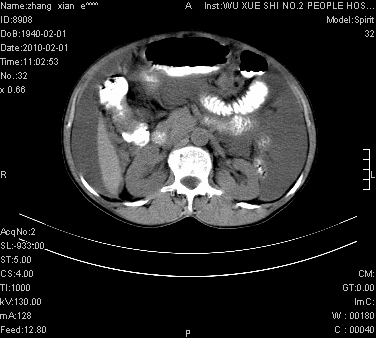

标题: CT24434:70岁 女 腹胀,腹水原因待查 [打印本页]

标题: CT24434:70岁 女 腹胀,腹水原因待查

大量腹水,脾脏囊性占位,子宫颈占位,右侧腹股沟淋巴结肿大,建议+c,先查妇科。

腹盆腔大量积液,子宫增大,子宫颈增大外形不规则,内见低密度影,膀胱后壁显示不清,右腹股沟肿大淋巴结,脾脏囊性占位,子宫颈占位,子宫颈癌?建议增强。

考虑子宫癌并腹水 脾囊肿

子宫、宫颈占位?转移性腹水?肝性腹水?脾脏囊性占位,囊肿?血管瘤?淋巴瘤?

考虑:1、腹膜转移,大量腹水;

2、脾占位性病变;

3、左侧卵巢占位性病变,建议增强进一步检查。